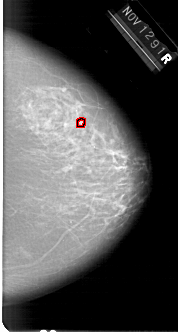

A_1648_1.RIGHT_MLO

RIGHT_MLO LINES 6871 PIXELS_PER_LINE 3976 BITS_PER_PIXEL 12 RESOLUTION 43.5 OVERLAY

FILE: A_1648_1.RIGHT_MLO.OVERLAY

TOTAL_ABNORMALITIES 1

ABNORMALITY 1

LESION_TYPE CALCIFICATION TYPE PLEOMORPHIC DISTRIBUTION CLUSTERED

ASSESSMENT 4

SUBTLETY 2

PATHOLOGY BENIGN

TOTAL_OUTLINES 1

BOUNDARY